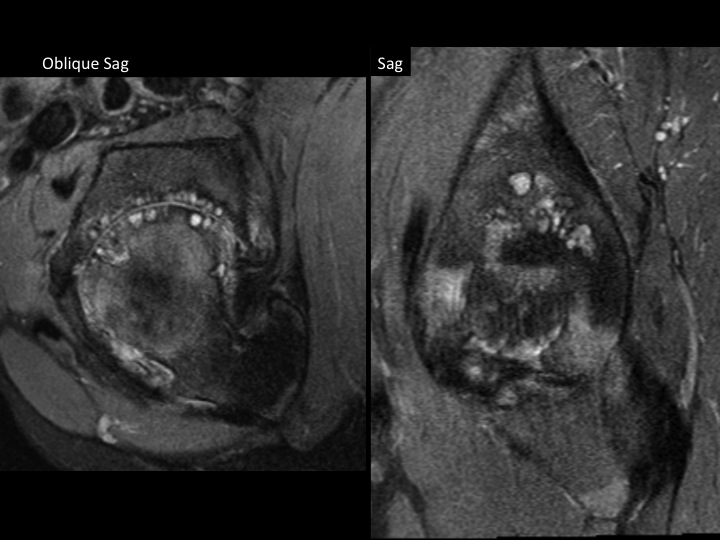

36M with DDH, chronic pain, recent onset more severe pain

I am asking for your thoughts. This is chronic DDH with severe secondary DJD. The femoral head is superiorly migrated with chronic degenerative remodeling of the FH and acetabulum. This brings the posteroinferior acetabular rim and lesser troch into close approximation and appears to cause some sort of impingement. Caudal to that site, there is isolated edema of what is either the Quad Femoris or possibly the Add Magnus (I am confused by the anatomic distortion), which cannot be due to direct muscle friction. I do not know if the Acetabular-Less Troch friction is the direct cause of symptoms, if that is causing nerve impingement, or if there is a muscle strain due to the abnormal stress of the deformity (seems least likely as the deformity is chronic). Please help.

acetabular-femoral impingement